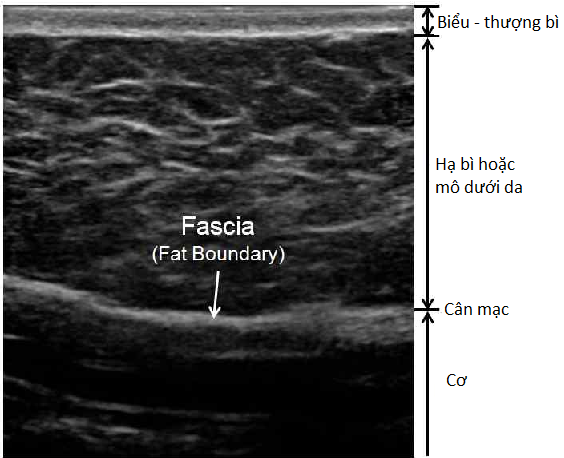

Bình thường mô dưới da có hình ảnh giảm âm với vài sợi tăng âm (là hình ảnh của các sợi liên kết). Ở trên lớp mô dưới da, có một lớp biểu - trung bì mỏng, tương đối tăng âm. Lớp cân mạc nằm sâu bên dưới mô dưới da.